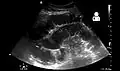

Small bowel obstruction on ultrasound[19]

-

Radiological signs of bowel obstruction include bowel distension (small bowel loops dilated >3 cm) and the presence of multiple (more than 2) air-fluid levels on supine and erect abdominal radiographs.[16] Ultrasounds may be as useful as CT scanning to make the diagnosis.[17]

Causes of bowel obstruction include adhesions, hernias, volvulus, endometriosis, inflammatory bowel disease, appendicitis, tumors, diverticulitis, ischemic bowel, tuberculosis and intussusception.[1][2] Small bowel obstructions are most often due to adhesions and hernias while large bowel obstructions are most often due to tumors and volvulus.[1][2] The diagnosis may be made on plain X-rays; however, CT scan is more accurate.[1] Ultrasound or MRI may help in the diagnosis of children or pregnant women.[1]